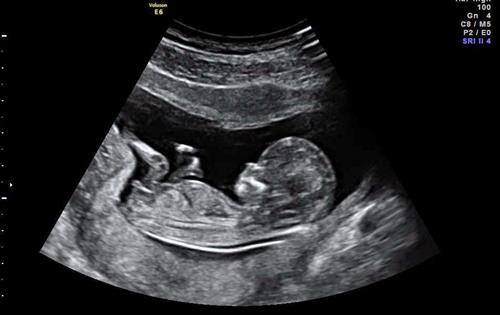

Phá thai vì thiếu hiểu biết là một lẽ thế nhưng có những trường hợp không mong muốn như khi soi siêu âm phát hiện thai nhi có dị tật bẩm sinh và được bác sĩ khuyên bỏ thì nên như thế nào. Hầu hết chúng ta trong hoàn cảnh đó đều rất thương tiếc nhưng đành phải bỏ đi. Thế nhưng theo khía cạnh nhân quả bạn nên tìm hiểu vấn đề này kỹ hơn. Ví dụ như trước đây khoa học không đủ phát triển, chúng ta không có máy dò siêu âm và đến khi hạ sinh mới biết vấn đề của con thì sao? Cuối cùng các gia đình đó vẫn nuôi và yêu thương con mình bất chấp hoàn cảnh. Chúng ta tưởng rằng bỏ thai nhi có dị tật là cách dẹp bỏ đi cái phiền não về sau thế nhưng cho dù đó không phải là duyên lành nhưng bố mẹ không có quyền chối bỏ nó. Bậc làm bố, làm mẹ nên thương cảm, thương đứa trẻ không được hoàn hảo ấy hơn là loại bỏ cơ hội sống của nó vì nếu không dù bỏ đi đứa trẻ tật nguyền trong bụng, theo nhân quả vẫn là càng làm tăng duyên ác cho bản thân.